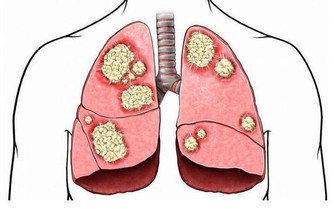

雖然炎症能在受傷的時候保護我們,但大家可能不知道,慢性炎症是非常危險的,它是包括心髒病、癌症在內的致命疾病的誘因。所以,在日常生活中吃一些抗炎食物,不僅可以幫我們減輕炎症帶來的疼痛,也有助於身體健康。